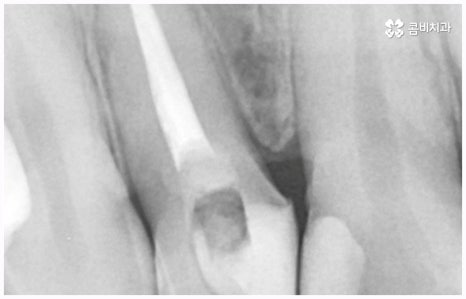

이러한 치아 상실에 대해 예전에는 틀니와 브릿지 시술을 많이 받았지만 요즘 대세는 임플란트 식립이라고 할 수 있어요. 틀니처럼 탈락의 위험이 잦거나 음식을 먹을 때 제약이 크게 따르지 않으며 브릿지처럼 양 옆 치아를 제거하지 않아도 되는 임플란트는 치아가 빠진 잇몸에 직접 티타늄 인공 치근(픽스처)을 심은 다음 지대주(연결 부위)를 이어주고 크라운(치아 머리 보철물)을 씌워 수복을 하는 것이기 때문에 저작 능력의 회복이 탁월하고 겉에서 봤을 때 거의 자신의 치아와 다름없이 자연스럽게 보인다는 장점으로 인해 많은 분들이 선호하시는 거예요.

비용이나 시간적인 부담이 만만치 않기 때문에 임플란트를 보다 오랜 기간 동안 건강하게 사용하려면 어떻게 해야 하는지 궁금해 하시는 분들이 많이 있으실 거예요. 임플란트 식립 성공률 및 지속률에 가장 크게 영향을 주는 것은 환자분들의 잇몸뼈 건강 상태 및 술자의 숙련도라고 할 수 있는데요. 예를 들어 구강 질환을 원인으로 한 병증이 심각하거나 치아를 상실한지 오랜 시간이 지나 잇몸뼈의 흡수가 많이 일어났기 때문에 높이와 밀도 등이 식립을 진행하기에 충분하지 않다면 뼈이식을 선행하여 기반부터 튼튼하게 보충해 줄 필요가 있어요. 또한 노화로 인해 상악동이 내려왔다면 상악동 거상술을 통해 공간을 확보해 주어야 하는데 이렇게 고난도 수술의 경우 다양한 임상 경험을 통해 풍부한 노하우와 뛰어난 기술력을 가지고 있는 의료진과 함께 하는 것이 무엇보다 중요하다고 할 수 있습니다.